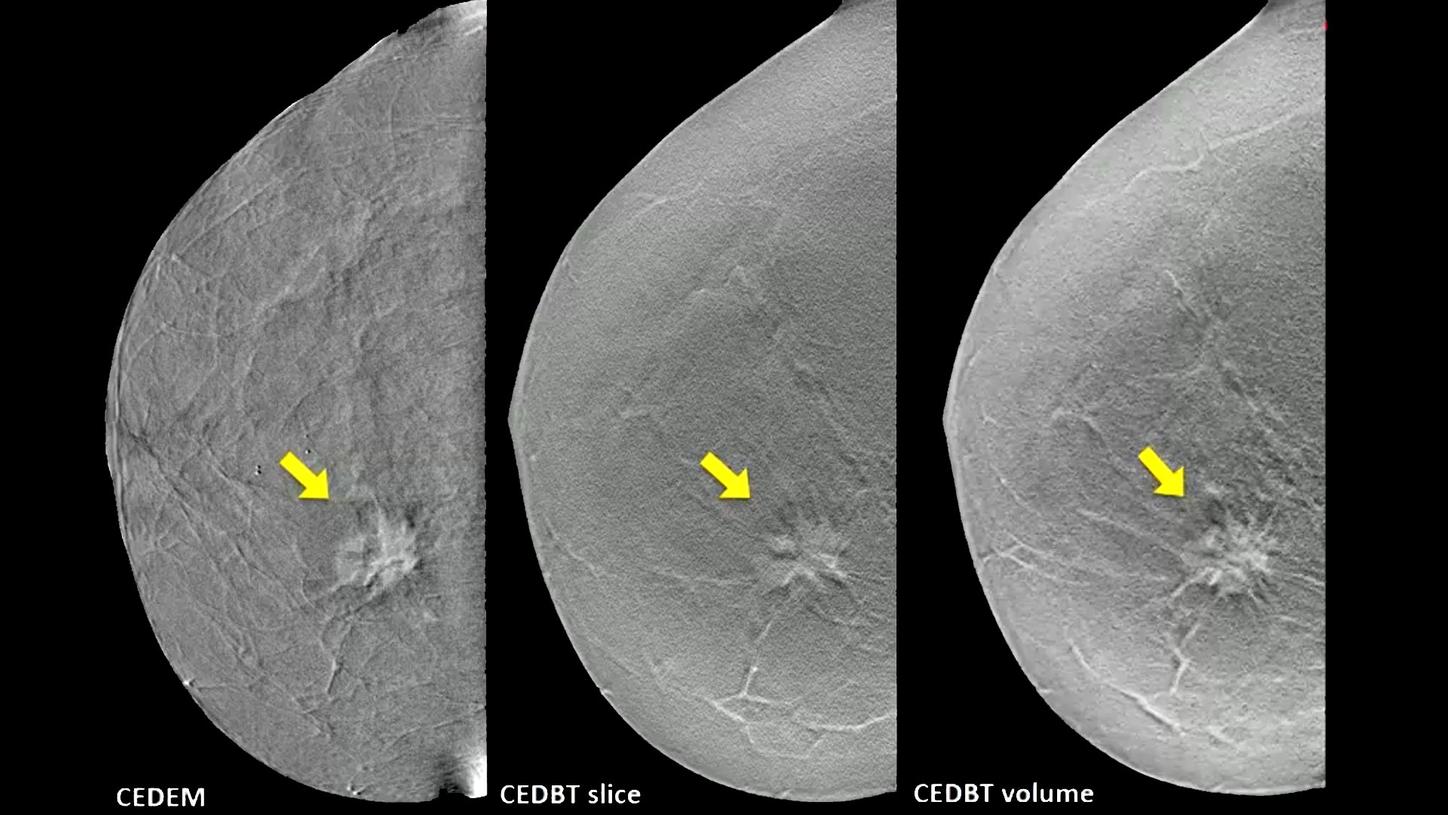

Our innovative portfolio of mammography systems and reading solutions provides the highest depth resolution diagnostic accuracy and enables personalized breast care – from screening to diagnostics to follow-up.